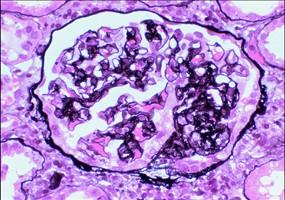

问题 下列不属于增生性肾小球肾炎的是 ( )

选项 A、硬化性肾小球肾炎 B、毛细血管内增生性肾小球肾炎 C、系膜毛细血管性肾炎 D、系膜增生性肾小球肾炎 E、新月体肾小球肾炎

答案 A